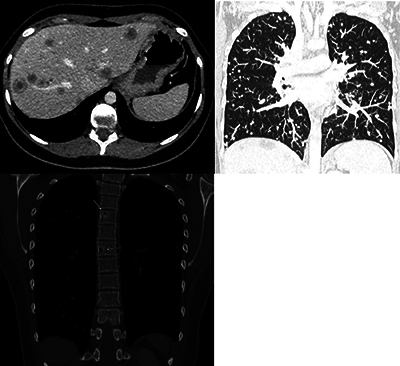

Abstract Image

Teaching point: When confronted with multifocal "metastasis-like" liver lesions without a known primary tumor, in particular in younger female patients, considering hepatic epithelioid hemangioendothelioma (HEHE) in the differential diagnosis can guide pathological examination and potentially avoid the need for multiple invasive biopsies.